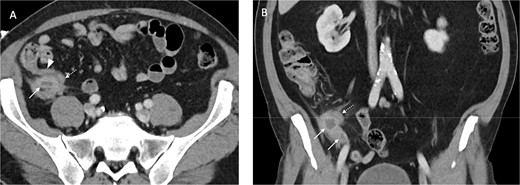

An inflamed appendix with peri-appendiceal stranding and a complex 23 × 20 × 27 mm collection at the apex of the appendix with opposed loop of small bowel with mural thickening

Acute cholecystitis with some areas of the gallbladder wall showing no enhancement (Fig. 2)

Contrast enhanced axial (A) and coronal (B) CT images in portal venous phase demonstrate periappendiceal abscesses (solid arrows) closely associated with thick-walled and inflamed tip of the appendix (dashed arrows). Note the normal appearing base of the appendix (arrowhead in A).